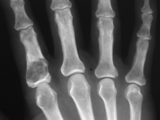

DJD-hand

DJD-hand